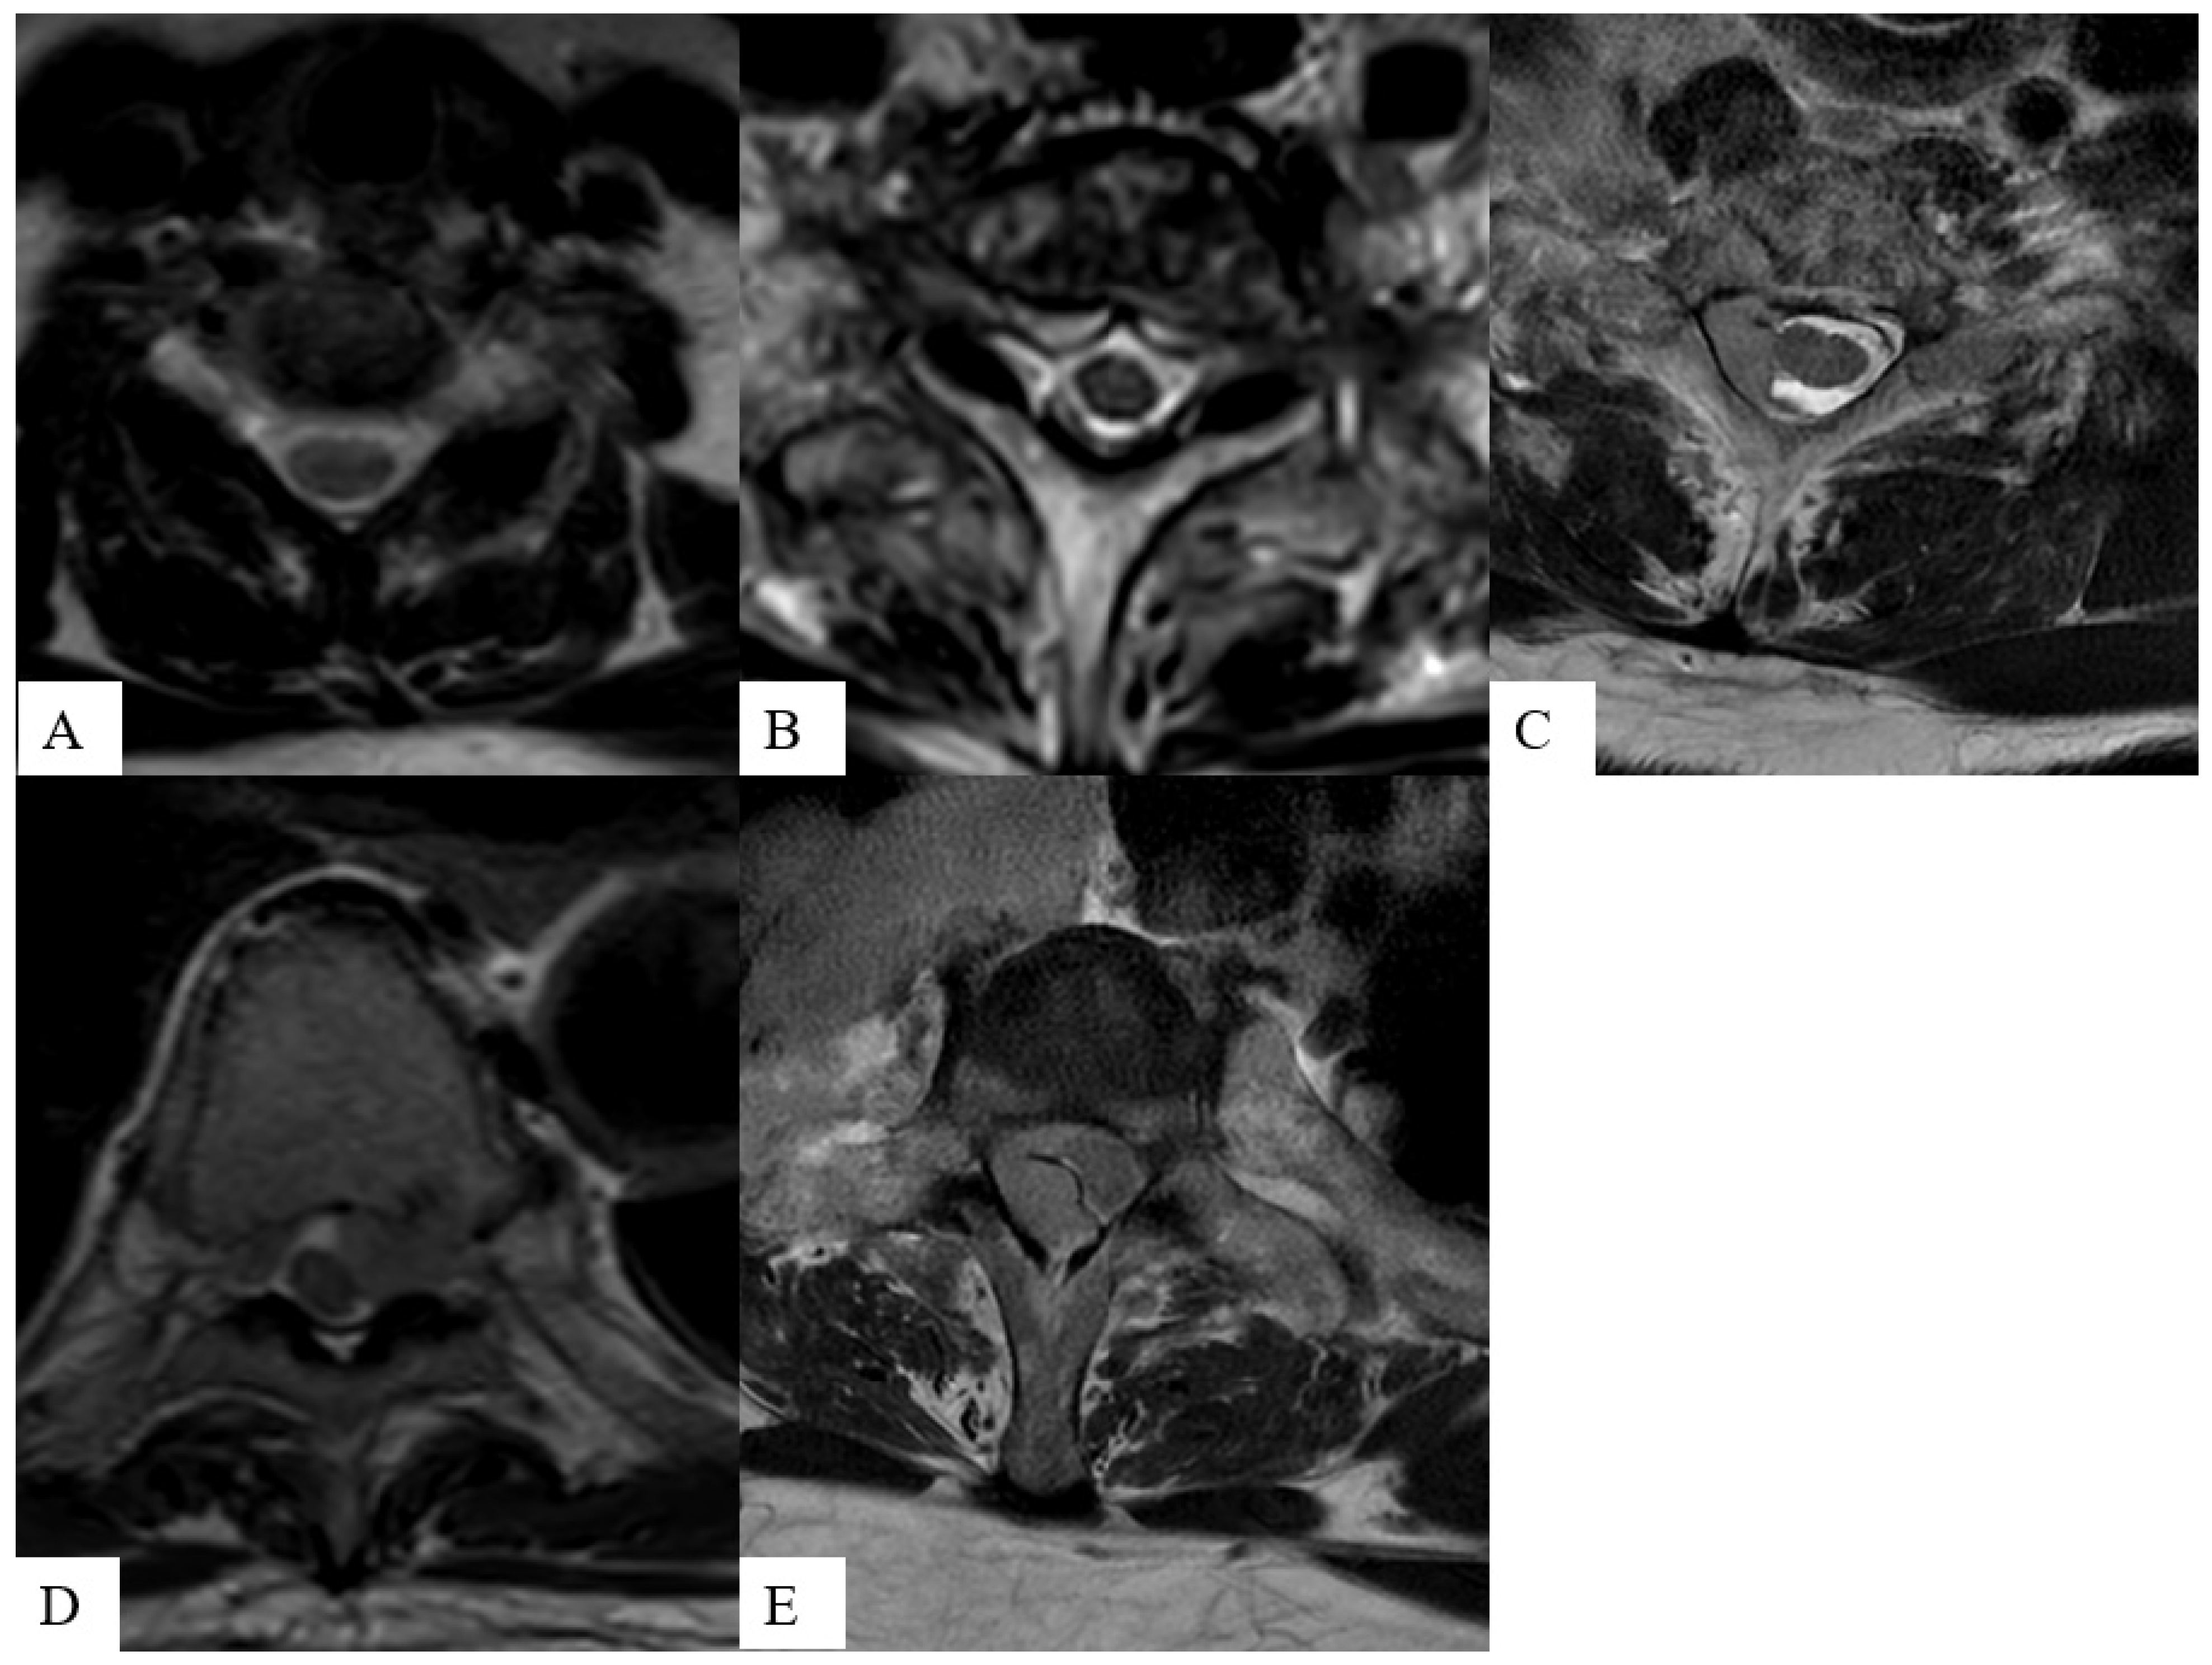

The ESCC score is assessed on axial T2-weighted images, which demonstrate superior inter- and intra-rater agreement when compared to T1-weighted and T1-weighted post-contrast acquisitions when used by a panel of expert reviewers [36] (examples shown in Figure 2). When combined with clinical and histopathological features, the ESCC score provides useful guidance for SMs therapy. ESCC scores of ≤1b are optimal candidates for primary SBRT. The optimal management of ESCC 1c-3 is case-specific, while spines with ESCC scores of 2 or 3 may undergo surgical intervention prior to SBRT to avoid neural complications, contingent on tumor radiosensitivity [10,36,37,38]. Spinal cord tolerance must be respected with underdosing as needed to achieve the constraints [39].

Figure 2.

Axial T2-weighted images demonstrate the increasing severity of the epidural space involvement in patients with spinal metastasis from images (A) to (E): ESCC grade 1a shows tumor spreading to epidural space without indenting the thecal sac (A); grade 1b shows tumor causing indentation of the thecal sac (B); grade 1c shows tumor abutting but not compressing the spinal cord (C); grade 2 shows tumor compressing the spinal cord (D); and grade 3 shows tumor completely obliterating the subarachnoid space (E).